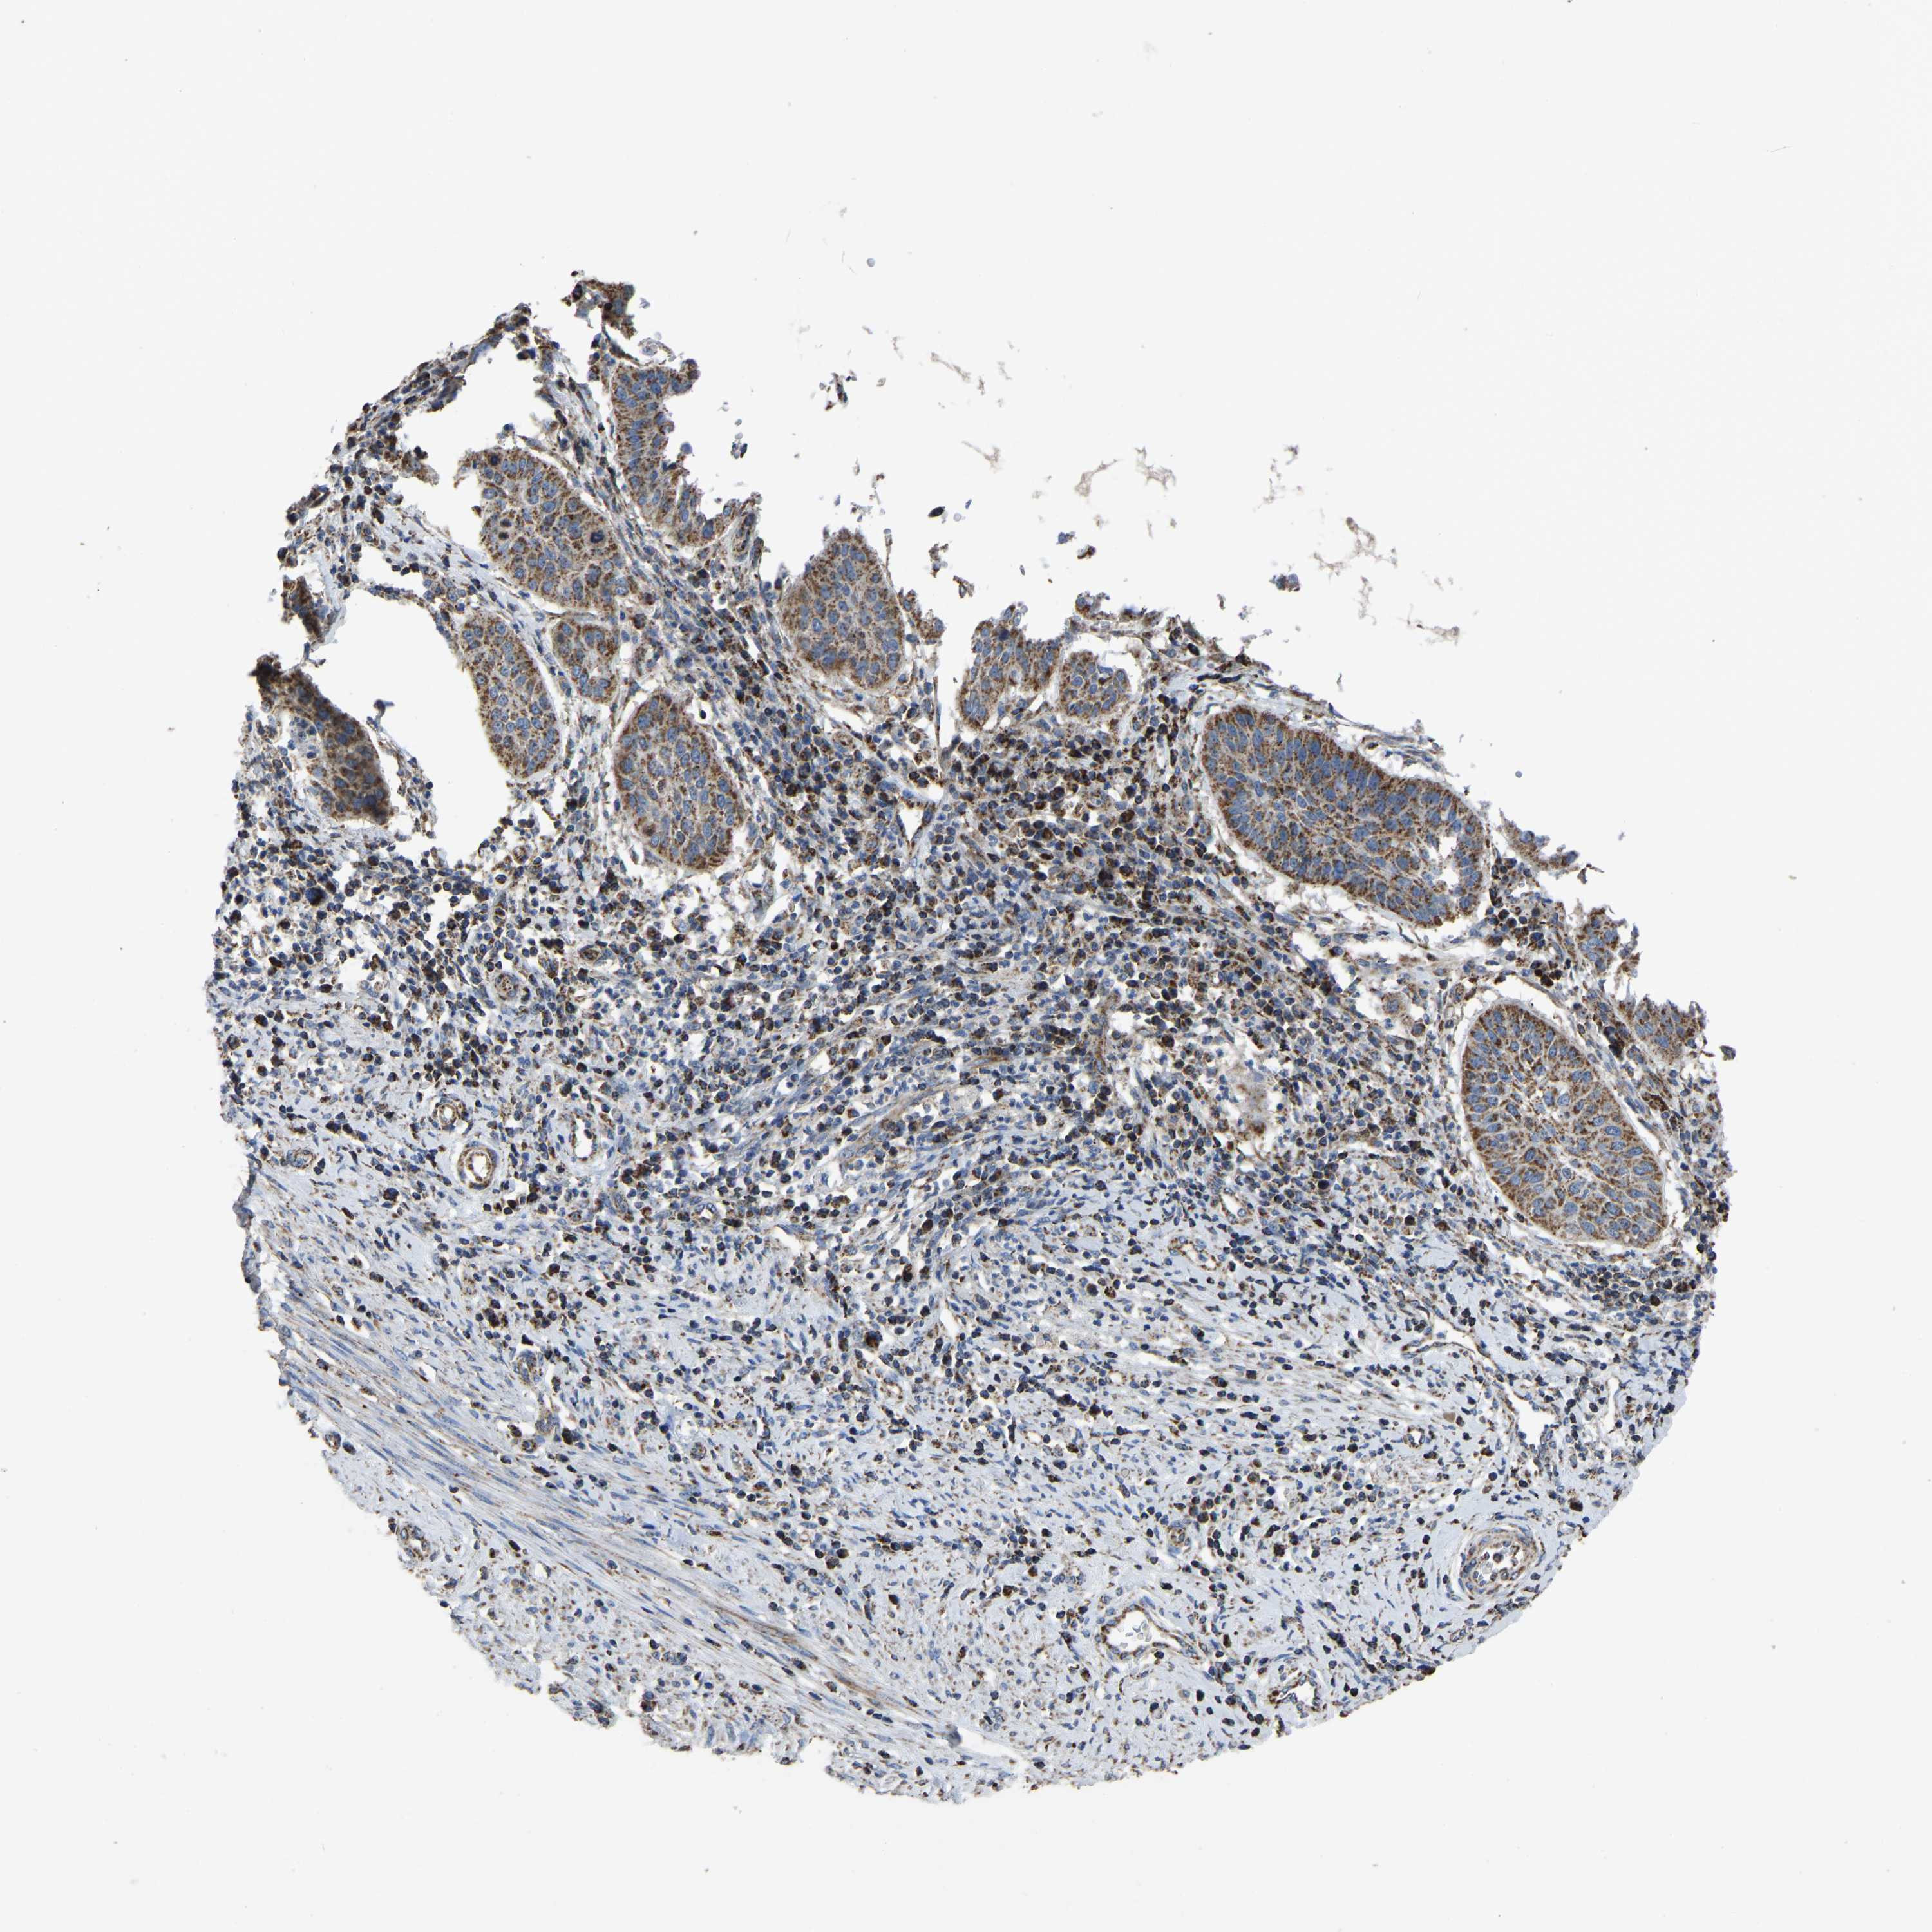

CERVICAL CANCER - Protein expressioni

A mouse-over function shows sample information and annotation data. Click on an image to view it in a full screen mode. Samples can be filtered based on level of antibody staining by selecting one or several of the following categories: high, medium, low and not detected. The assay and annotation is described here.

Note that samples used for immunohistochemistry by the Human Protein Atlas do not correspond to samples in the TCGA dataset.

Antibody stainingi

Antibody staining in the annotated cell types in the current human tissue is reported as not detected, low, medium, or high, based on conventional immunohistochemistry profiling in selected tissues. This score is based on the combination of the staining intensity and fraction of stained cells.

Each image is clickable and will lead to virtual microscopy that enables deeper exploration of all samples and also displays staining intensity scores, fraction scores and subcellular localization as well as patient and tissue information for each sample.

Antibody HPA018990

Antibody HPA018993

Antibody HPA018996

Antibody HPA024089

Squamous cell carcinoma, NOS